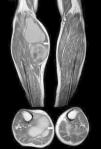

Paciente varón de 83 años, con artrosis, que acude a urgencias por cuadro agudo inflamatorio de la pierna que simula trombosis venosa profunda. En la exploración física se palpa gran masa de consistencia elástica, no pulsátil, dolorosa, en el hueco poplíteo, que se extiende hacia la pierna (fig. 1). Se plantea el diagnóstico diferencial con quiste de Baker. Se practica, como técnica de elección, una ecografía. El modo Doppler-color muestra permeabilidad del sistema venoso profundo. La ecografía musculoesquelética evidencia colección bien definida, adyacente al vientre medial del músculo gastrocnémico, llena de ecos difusos, predominantemente de baja amplitud (fig. 2). A pesar de no ser un aspecto infrecuente, las dimensiones de la tumoración hacen que la ecografía no resulte suficiente y se decide realizar RM específica de rodilla con secuencias potenciadas en T1, secuencias T2* (figs. 3–5) y tras la administración de contraste por vía intravenosa, confirmando la existencia de quiste de poplíteo gigante de 17×9cm. El paciente es tratado de forma conservadora, pautando en primer lugar antiinflamatorios no esteroideos, mejorando clínicamente y encontrándose actualmente asintomático, transcurridos los 6 primeros meses. Por dicho motivo, junto con la edad del paciente y a pesar de que el quiste apenas ha modificado su tamaño, se desestima, de momento, tratamiento quirúrgico.